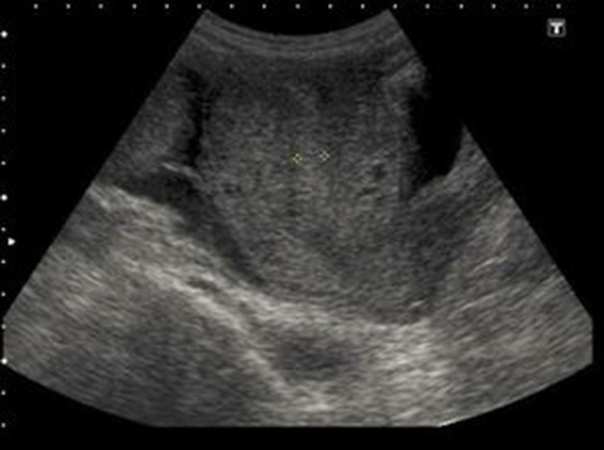

При осмотре: в толще барабанных перепонок пузырьки воздуха, признаков отека или воспаления нет. Аудиография: умеренная кондуктивная тугоухость справа, нормальный слух слева.